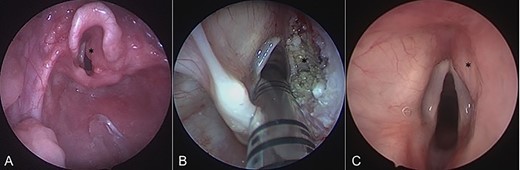

On admission, his oxygen saturations, serum haematology and biochemistry were normal. There was no daytime respiratory distress. At night, he had audible inspiratory stridor, a raised respiratory rate, tracheal tug and apnoeas. He underwent a diagnostic microlaryngoscopy, which showed a large, submucosal, nodular tumour involving the right aryepiglottic fold, false cord, ventricle and the medial wall of the piriform fossa (Fig. 2A). Histological analysis of biopsies described multiple tortuous nerve fascicles; the clinical suspicion of a plexiform neurofibroma was confirmed.

Intraoperative endoscopic images of the supraglottis: (A) before intervention; (B) after debridement; and (C) at 16 months after surgical intervention. Asterisk denotes area of interest.

The case was discussed in the Head and Neck multi-disciplinary team (MDT) meeting. Due to the patient’s age, co-morbidities and the site of the lesion, the MDT felt that complete surgical excision—requiring resection of the right aryepiglottic fold, false cord and ventricle—would result in significant morbidity. The child would be at risk of aspiration, dysphagia, dysphonia and laryngeal scarring. Therefore, we opted to use a coblation technique to debulk the neurofibroma (Fig. 2B).

Sixteen months after the second debridement, the patient had a largely asymptomatic airway, stable disease on MRI scans (Fig. 1B) and no signs of significant lesional growth or airway obstruction on repeat microlaryngoscopy (Fig. 2C). At 30 months follow-up, imaging shows the neurofibroma to have mildly increased in size but there are no significant respiratory symptoms and no functional impairment.